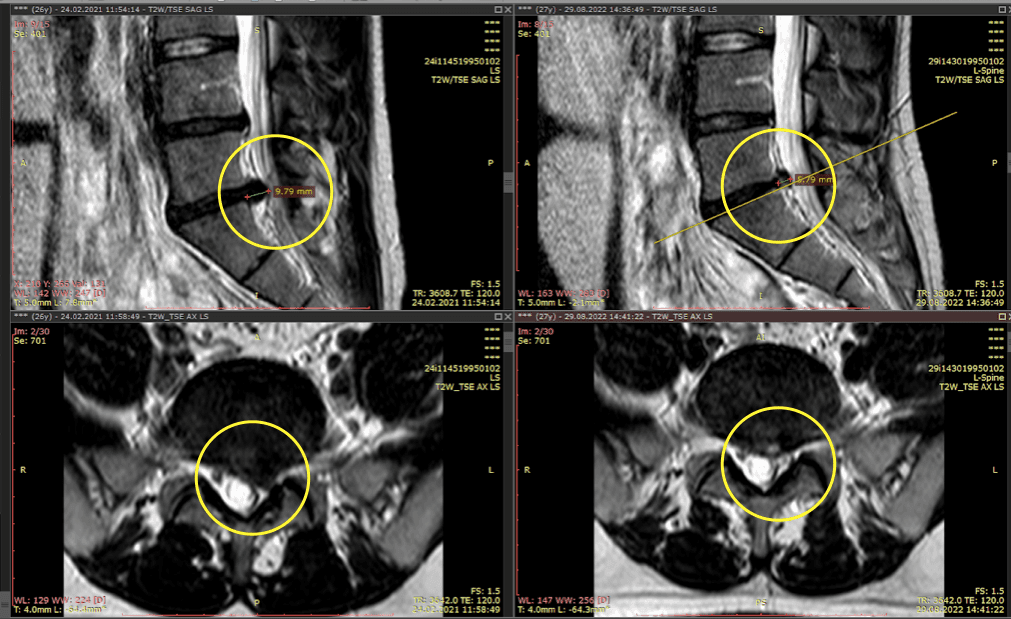

Метод лікування грижі шляхом стимуляції резорбції в Україні був впроваджений у 2020-2021 роках.  Алгоритм оцінки грижі на предмет резорбції, що використовується у клініках – є авторським, розроблений лікарем Боханом А.Ю.